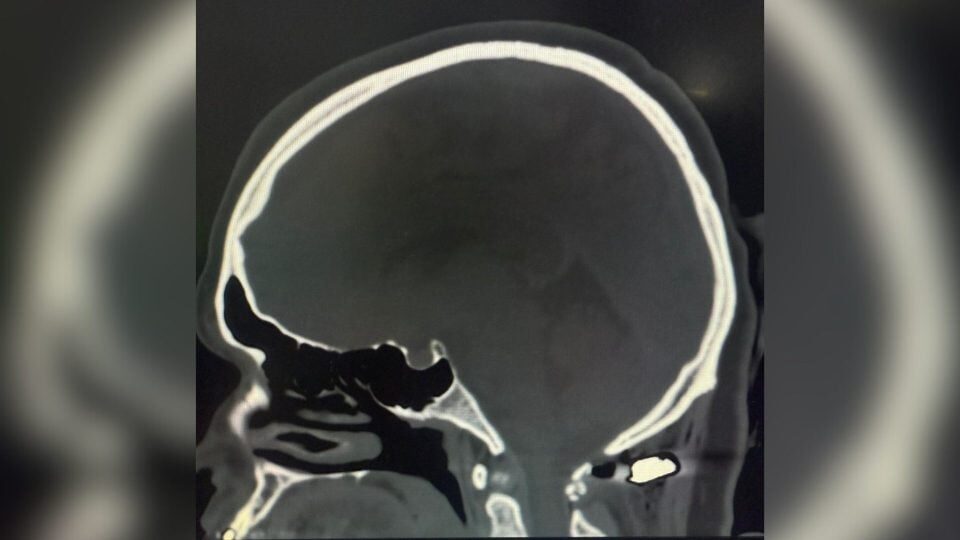

Mulher atingida na nuca por bala perdida no PR teve projétil alojado a 4 mm da medula cervical e escapou da tetraplegia

A mulher baleada na nuca durante um tiroteio em uma distribuidora de bebidas de Colombo, na Região Metropolitana de Curitiba, sobreviveu por um “milagre”, segundo médicos que a atenderam no Hospital Angelina Caron, em Campina Grande do Sul. Juliette Pires dos Santos Scrok, de 36 anos, teve o projétil alojado a apenas 4 milímetros da medula cervical e chegou andando e lúcida ao hospital, segundo o neurocirurgião responsável pelo atendimento.

De acordo com o médico, a equipe de neurocirurgia foi acionada após a paciente dar entrada com um orifício de entrada de tiro na região posterior do pescoço, mas sem saída aparente. O que mais chamou atenção dos profissionais foi o estado em que ela chegou.